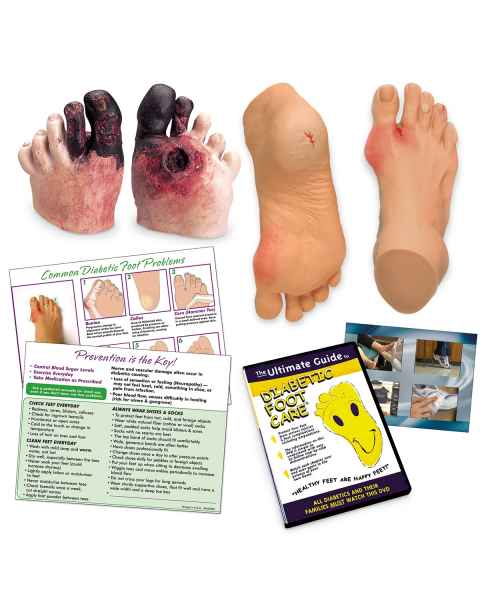

With the assistance of extremity anatomy models, patients and students have a tangible tool to better understand their appendages, as well as potential injuries that are afflicting them or require treatment. Our extensive selection of extremity models includes arm anatomical models, foot models, hand anatomy models, and leg models.